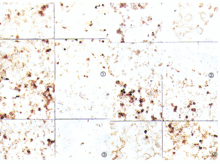

凝集素Kivela和Farkkanen(1987)發現在人視網膜,PNA標記視錐細胞而不標記視桿細胞。在乳腺、乳腺上皮細胞呈PNA陽性反應而肌上皮細胞和間質細胞呈PNA陰性反應。以多種凝集素對小鼠、大鼠和兔的腎組織切片進行染色結果表明,刀豆素A和蓖麻素存在於腎臟的各部,PNA和雙花扁豆凝集素(DBA)主要分布於遠曲小管和集合小管上皮細胞,荊豆凝集素(UEA)主要分布在血管內皮細胞,而麥芽素分布在腎小球。套用DBA對RIII和DDK品種的小鼠研究表明,DBA主要結合在各種組織內毛細血

管內皮細胞上,電鏡觀察顯示DBA結合在內皮細胞的表面,在趣的是在RIII品系小鼠某些組織的內皮細胞顯示肯定的DBA陰性反應,說明同一種屬動物的血管內皮細胞也存在有組織特異性的差別。Streit和Kreutzberg(1987)發現Griffonia Simplicifolia凝集素特異性標記面神經節內的小膠質細胞,其它類型的膠質細胞如星狀膠質細胞(astrocyte)等都顯示陰性反應。在切斷面神經後,增殖的小膠質細胞對Griffonia Simplicifolia凝集素的反應加強,免疫電鏡觀察表明,凝集素主要沉積在細胞膜或小膠質細胞突起的軸膜表面,特異性結合糖基是α—D—半乳糖。上海醫科大學附屬腫瘤醫院免疫病理室套用12種凝集素(表6-1)對人胚胎及各種正常組織進行了系統的凝集素受體的定位研究,結果表明,凝集素受體的分布並無即定規律可尋。如胃黏膜主細胞為PNA受體,而壁細胞為BSL受體,雙花扁豆受體(DBA)主要出現在大腸部份。